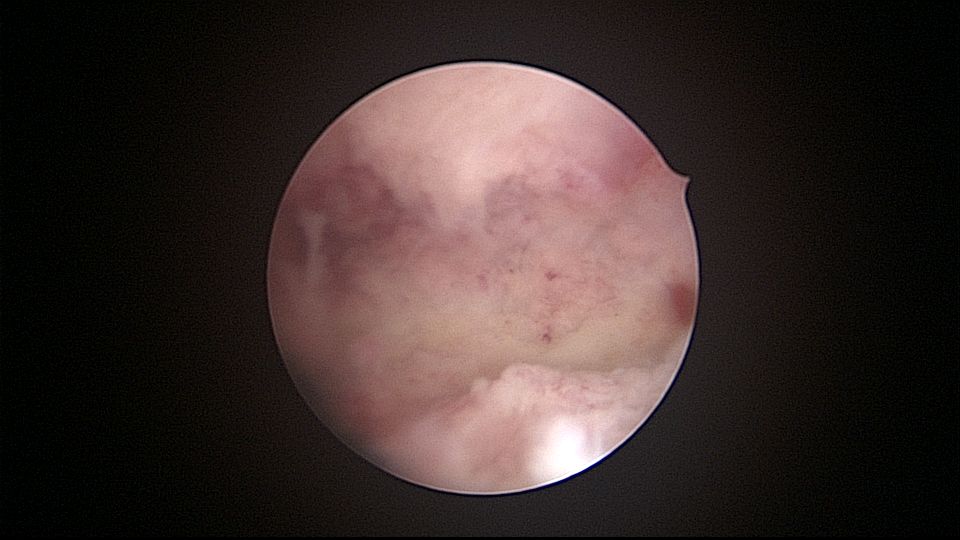

患者32岁,G6P2,顺产2次。2025年3月,停经56天,计划外妊娠,要求终止妊娠并放置节育环,考虑终止妊娠后宫腔大,担心环移位或脱落,要求固定节育环。γ环没有尾丝,用4号丝线连接环及不锈钢挂钩,将挂钩插入宫底肌层固定,异物钳原位固定曼月乐,退出宫腔镜,结束手术。术后患者未回院复查节育环位置。